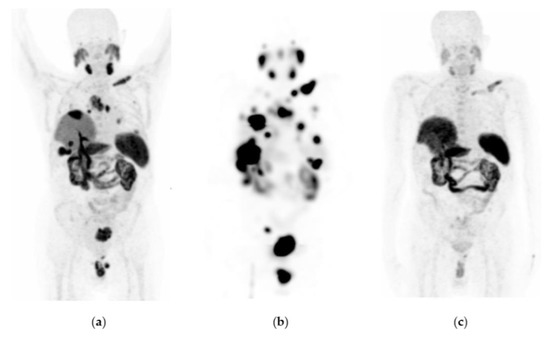

Figure 2. Patient with progressive and metastatic castration-resistant prostate cancer (mCRPC): (a) 68Ga-iPSMA PET/CT imaging before 177Lu-iPSMA therapy; initial levels of hemoglobin (15.5 g/dL), leucocytes (5700/µL), creatinine (0.82 mg/dL), platelets (238,000/µL), and serum PSA (129 ng/mL). (b) 177Lu-iPSMA SPECT imaging (first dose). (c) 68Ga-iPSMA PET/CT imaging eight months after the first 177Lu-iPSMA dose was administered; levels of hemoglobin (13.4 g/dL), leukocytes (3900/µL), creatinine (0.79 mg/dL), platelets (277,000/µL), and serum PSA (1.5 ng/mL). The patient responded completely to 177Lu-iPSMA therapy (four doses every six weeks; 7.4 GBq/dose).

Figure 3. Patient with progressive and metastatic castration-resistant prostate cancer (mCRPC): (a) 68Ga-iPSMA PET/CT imaging before 177Lu-iPSMA therapy; initial levels of hemoglobin (11.1 g/dL), leucocytes (4900/µL), creatinine (0.88 mg/dL), platelets (115,000/µL), and serum PSA (84.7 ng/mL). (b) 177Lu-iPSMA SPECT imaging (first dose). (c) 68Ga-iPSMA PET/CT imaging 10 months after the first 177Lu-iPSMA dose was administered; levels of hemoglobin (10.1 g/dL), leukocytes (2100/µL), creatinine (0.91 mg/dL), platelets (87,000/µL), and serum PSA (7.7 ng/mL). The patient responded partially to 177Lu-iPSMA therapy (four doses every six weeks; 7.4 GBq/dose).

177Lu-iPSMA showed an overall response rate of 36.6% (Table 2). Figure 2 and Figure 3 show typical clinical cases of complete response (disappearance of all lesions or adenopathies less than 10 mm short axis) and partial response (decrease of at least 30% in the sum of the largest diameters of lesions compared with the baseline study) after 177Lu-iPSMA therapy. In addition, the reduction of large tumors and multiple metastatic lesions are proof of the high specificity and molecular recognition of 177Lu iPSMA by PSMA at the tumor cell level (Appendix A) (Figure A1, Figure A2 and Figure A3).